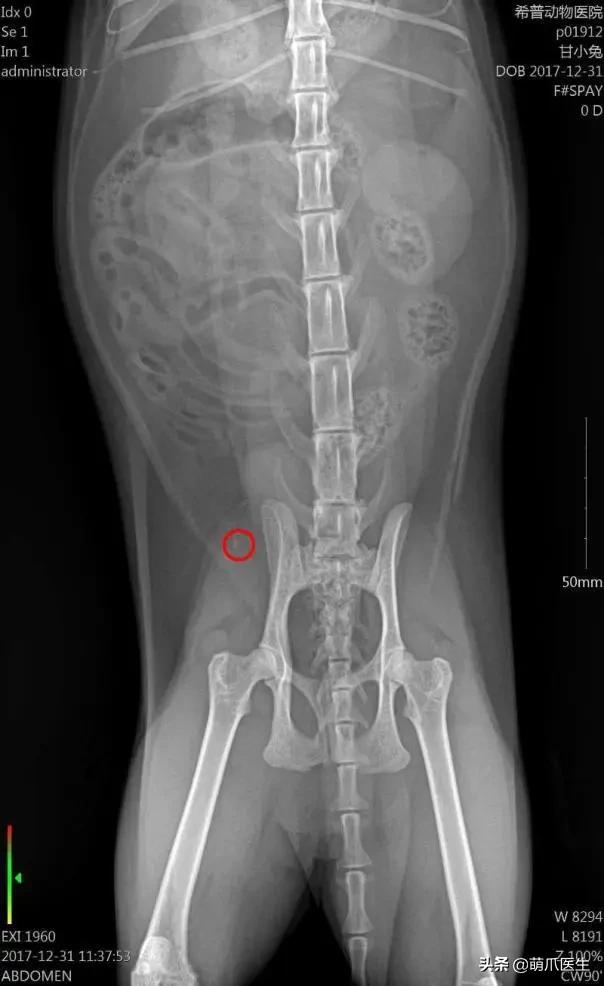

膀胱结石(X线片)